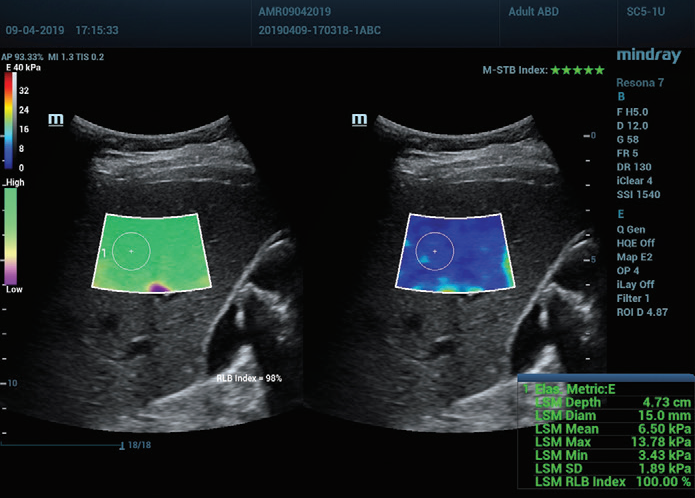

Рисунок 1 (продолжение): (e) Изображения, полученные с помощью 2D SWE (STE; Mindray, Шэньчжэнь, Китай). Приводятся два критерия качества: индекс стабильности (M-STB), отображаемый звездочками (наибольшая стабильность- пять звездочек зеленого цвета), и карта надежности (RLB), с цветами от фиолетового до зеленого - последний означает высокую надежность. Звездочки являются индикатором движения во время получения данных. Если количество отображаемых звездочек менее четырех, значит, во время получения данных наблюдается значительное движение, и этот кадр не следует использовать для измерения жесткости ткани печени. (f) Полученные изображения

Таким образом, технология Sound Touch Elastography (STE) компании Mindray обеспечивает высокую надежность результатов измерений, получаемых во время исследования с помощью 2D-эластографии сдвиговой волной, благодаря коэффициентам качества и достоверности, включая индекс стабильности (M-STB), карту надежности (RLB), индекс надежности (RLB), и т. д.

Индекс M-STB указывает на наличие/степень помех, вызванных дыханием пациента или движениями оператора. Индикатор представлен в виде звездочек (наибольшая стабильность- пять звездочек зеленого цвета), надежное изображение должно иметь ≧4 зеленых звездочки.

Карта RLB указывает на надежность изображений STE, ее цвет меняется от фиолетового к зеленому, последний указывает на высокую надежность. При коэффициенте RLB ≧90% изображение является надежным.